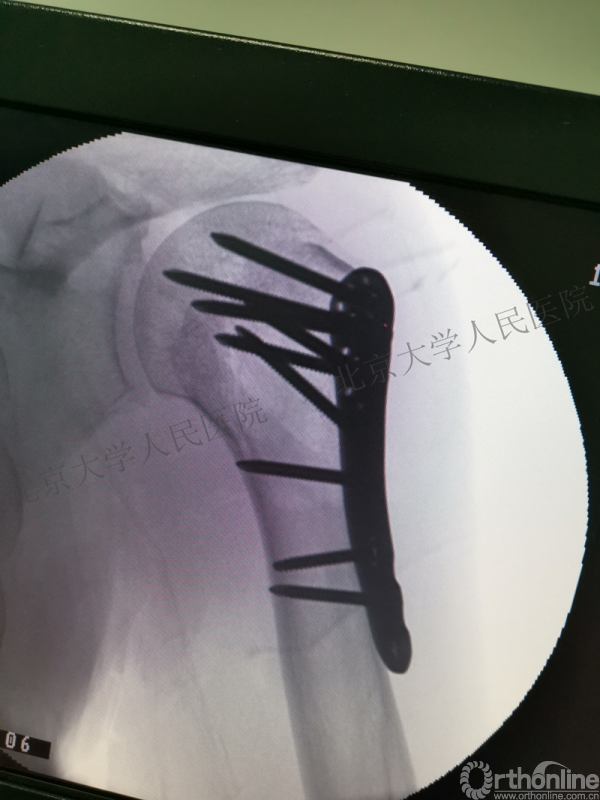

术后影像学检查

全麻下行切开复位内固定术,备植骨+关节镜检

胸大肌三角肌间隙入路